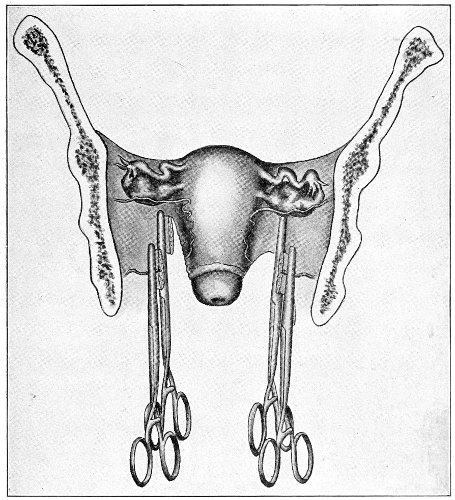

An accurate knowledge of the anatomy and mechanism of the female perineum is essential to an understanding of the nature and treatment of injuries to this structure. The anatomical structures lying between the anus behind and the symphysis pubis in front are those that most directly interest the gynecologist. Proceeding from 57 below upward, we find the following structures lying in superimposed planes: the skin, the superficial fascia, the deep layer of the superficial fascia, the transversus perinæi and the sphincter vaginæ muscles, the anterior layer of the triangular ligament, the posterior layer of the triangular ligament, the levator ani muscle (Fig. 19).

The injuries to the perineum that may result from childbirth are classified according to the position or the direction and extent of the laceration. They are as follows: slight median tear; median tear involving the sphincter ani; tear in one or both of the vaginal sulci; subcutaneous laceration of the muscles and fascia.

All these injuries demand operative treatment. The operation for the repair of injuries to the perineum is called perineorrhaphy. It is called immediate or primary, intermediate, and secondary perineorrhaphy, according to the time after the receipt of the injury at which the operation is performed. The primary operation is done during the first twenty-four hours. The primary operation should always be performed. A careful inspection of the perineum and the posterior vaginal wall should always be made after labor, and any laceration should be repaired within twenty-four hours. The advantages of the primary operation are many. The parts are usually so numb that it is not necessary to administer an anesthetic. No denudation is necessary, and therefore no tissue need be sacrificed. The woman is spared the pain and discomfort of granulation and cicatrization.

The bad results that follow neglect of the primary operation are very numerous, and will be studied hereafter. The injured muscles retract, and, being functionally useless, undergo atrophy, and when finally repaired never possess their former strength. Involution in the vagina and the uterus may be arrested, and all the disasters incident to subinvolution may appear. Vaginal and uterine prolapse occur; the natural supports of the 63 vagina and uterus become stretched, and, though afterward the perineum may be restored, yet it may be found impossible to retain the uterus in its proper position. It is always good surgery to repair an injury as soon as possible.

When practicable, a certain amount of preparation of the patient should be made before the operation of perineorrhaphy. This is most easily effected before the intermediate and secondary operations. The vagina and the vulva should be sterilized, and the intestinal tract should be emptied. Thorough evacuation of the bowels is most important when the sphincter ani has been injured, because it is desirable, after operation for this lesion, that the bowels should not be moved for five or six days. A saline purgative should be administered on an empty stomach about five hours before the operation, and a rectal injection of soap and water should be administered about one hour before the operation. Whatever purgative be employed, it should be administered at such a time that its action shall have ceased by the time of the operation. If this precaution is not observed, there may be a discharge of feces that will infect the wound and interfere with the manipulations.

For operation upon the perineum the woman should be placed in the dorso-sacral position (Fig. 1, page 23).

The special forms of operation will be discussed in the consideration of the varieties of perineal injury.

Slight Median laceration of the Perineum.—In this injury the tear takes place through the fourchette. Posteriorly it may extend as far as the sphincter ani muscle. Upward it may extend for an inch up the posterior vaginal wall. The appearance of this tear is shown in Fig. 33. It will be noted that, as this tear takes place in the median line, none of the muscles that support the perineum are involved, nor are the planes of fascia injured. The perineum is slightly split, and the insertions and origins of the muscles and the fascia are slightly separated. The supporting structures of the perineum and the pelvic floor are, however, uninjured.

Fig. 33.—Recent slight median laceration of the perineum: sutures introduced.

If this tear is detected after labor, it should be closed by the immediate operation. A slight tear involving chiefly the cutaneous aspect of the perineum should be closed by three or four sutures introduced from the outside, as in Fig. 33. The needle should be introduced about a quarter of an inch from the edge of the wound. It should not be passed parallel with the plane of the lacerated surface, but should be swept outward and then inward toward the 68 angle at the bottom of the tear (Fig. 34). It may either emerge at the angle and be re-introduced, or it may be passed directly through to the skin-margin on the opposite side of the wound. If the suture is passed in this way, there will be perfect apposition throughout the whole surface of laceration. If the sutures are improperly passed, there may result only apposition of the skin-edges.

Fig. 34.—Diagram representing the correct and the incorrect method of passing the suture for closure of slight perineal laceration.

If the laceration extends up the posterior vaginal wall, two sets of sutures must be introduced—one on the vaginal aspect of the tear, and one on the skin aspect (Fig. 35).